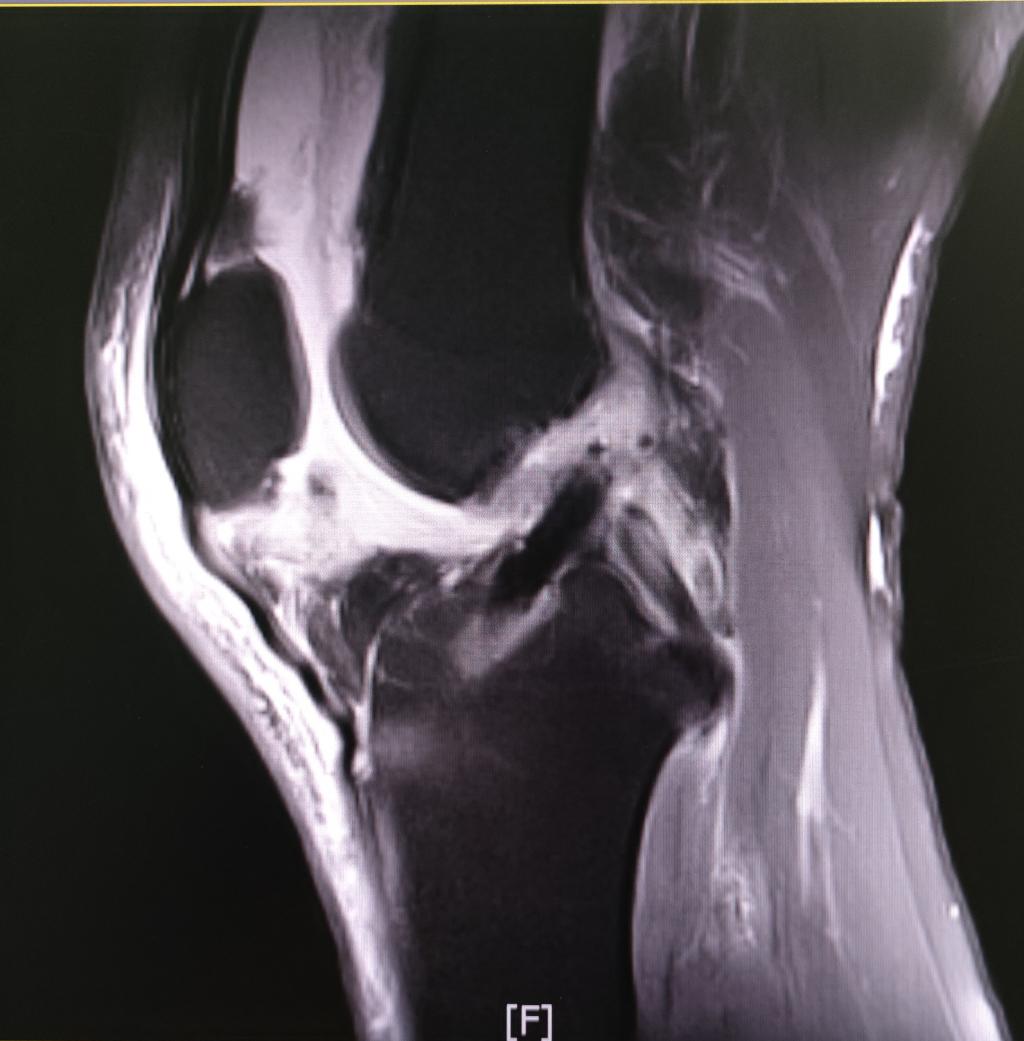

术后复查核磁

ACL的保残重建,区别于传统重建时完全去除韧带残存纤维的方式,可很好的保留残存韧带中的血液循环及本体感受器,不但能更快的促进移植韧带的成熟愈合,还可以大大提高最终的功能恢复程度。多年来已经成为骨一科的一项特色技术,收治的多名高水平运动员都在术后重返赛场,再创佳绩。然而,由于术中视野不佳、骨道定位困难等因素,对术者经验和技术的要求较高,操作相对复杂,推广较为困难,国内开展的单位相对较少。ACL的全内重建技术是国际上新近发展出现的另一项新技术,相比传统方法,它可有效的保留骨质,更精准的建立骨道,需要的肌腱移植材料更少,最大程度上避免了术后膝关节屈膝力量及内旋功能的下降,保护了受伤膝关节的原有功能,且创伤更小,康复更快,术后疼痛更少。骨一科运动医学团队在近年来的临床实践中发现,全内重建中所应用的股骨及胫骨的骨道逆行制备技术,恰恰可以解决保残重建中的视野不佳及骨道定位困难的问题,骨一科自行设计的“全内联合保残“新技术,不仅完美结合了两种技术的优点,让整个手术流程变得更加流畅,也大大提高了患者的术后疗效,对运动需求较高的年轻人和运动员具有更重要的意义。